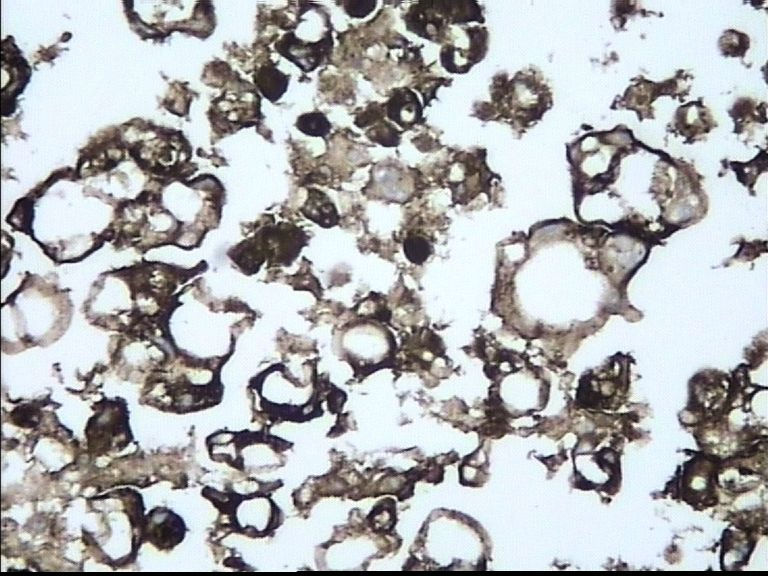

67岁 男 胸水组织块

• 67岁 男 胸水组织块图1

图1

TTF-1

ck7

CEA

肺腺癌细胞

肺腺癌